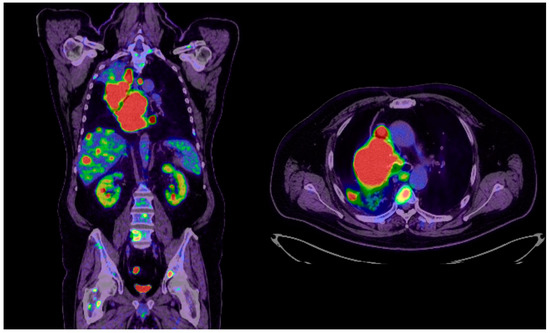

2. Case Presentation